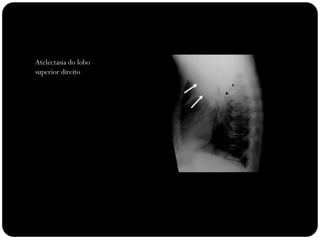

Atelectasia do lobo

superior direito

Atelectasia do Lobo Sup. D.

O que está anormal?

Atelectasia LSD

Sinal do S de Golden

Causado por

carcinoma

broncogênico

Note deslocamento

da fissura menor,

elevação da cúpula

diafragmática

direita...